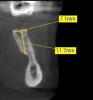

sergio Опубликовано 13 июня, 2013 Поделиться Опубликовано 13 июня, 2013 Вот такое язычное поднутрение в позиции 36, 37 КТ было сделано в прикусе.Высота до антагонистов мала для цементной фиксации, поэтому провел остеопластику фрезой.При засверливании на середине пути пальцем с язычной стороны стал чувствовать фрезу. Сверлил на 10 мм глубиной. Один имплант Альфа Био поставил длиной 8 мм, второго не было, пришлось ставить 10 мм. Вот и думаю теперь, может надо было с язычной отслоить слизистую побольше и мембрану подсунуть или ничего страшного. Язычнее импланты не было возможности заваливать, чтобы ортопед потом не матерился Ссылка на комментарий

doktorenok Опубликовано 23 июня, 2013 Поделиться Опубликовано 23 июня, 2013 Вот такое язычное поднутрение в позиции 36, 37 5лет как отпротезировано-полет нормальный Ссылка на комментарий

IvanK Опубликовано 23 июня, 2013 Поделиться Опубликовано 23 июня, 2013 5лет как отпротезировано-полет нормальныйПерфо.JPGТам такая картикалка, что не заметить при сверлении не возможно было.. или это нарочно?Какова длина имплантата? Ссылка на комментарий